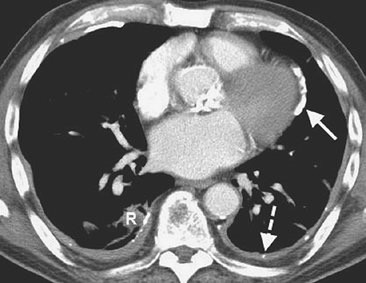

FIGURE 9-5. Cerebrospinal fluid leak into pleural space. A: PA chest radiograph of a 42-year-old man who recently underwent partial corpectomy of the thoracic spine at several levels shows complete opacification of the right hemithorax and shift of the mediastinum to the left. B: Non–contrast-enhanced CT shows a large right pleural effusion, collapse of the right lung, mediastinal shift to the left, findings of corpectomy, and continuity of fluid from the spine into the pleural space (arrow).